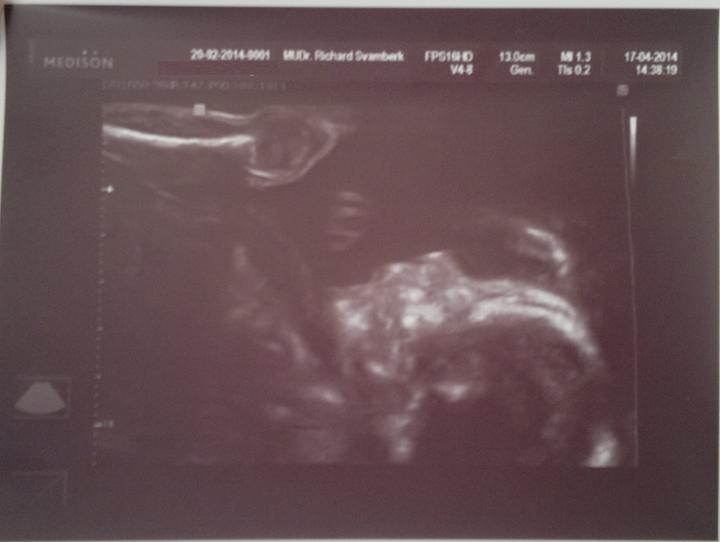

Jáchym Pavel Kolařík - 2. těhotenství

Termín porodu dle PM - 29. 8. 2014

( porod byl skutečně 24. 8. 2014 )